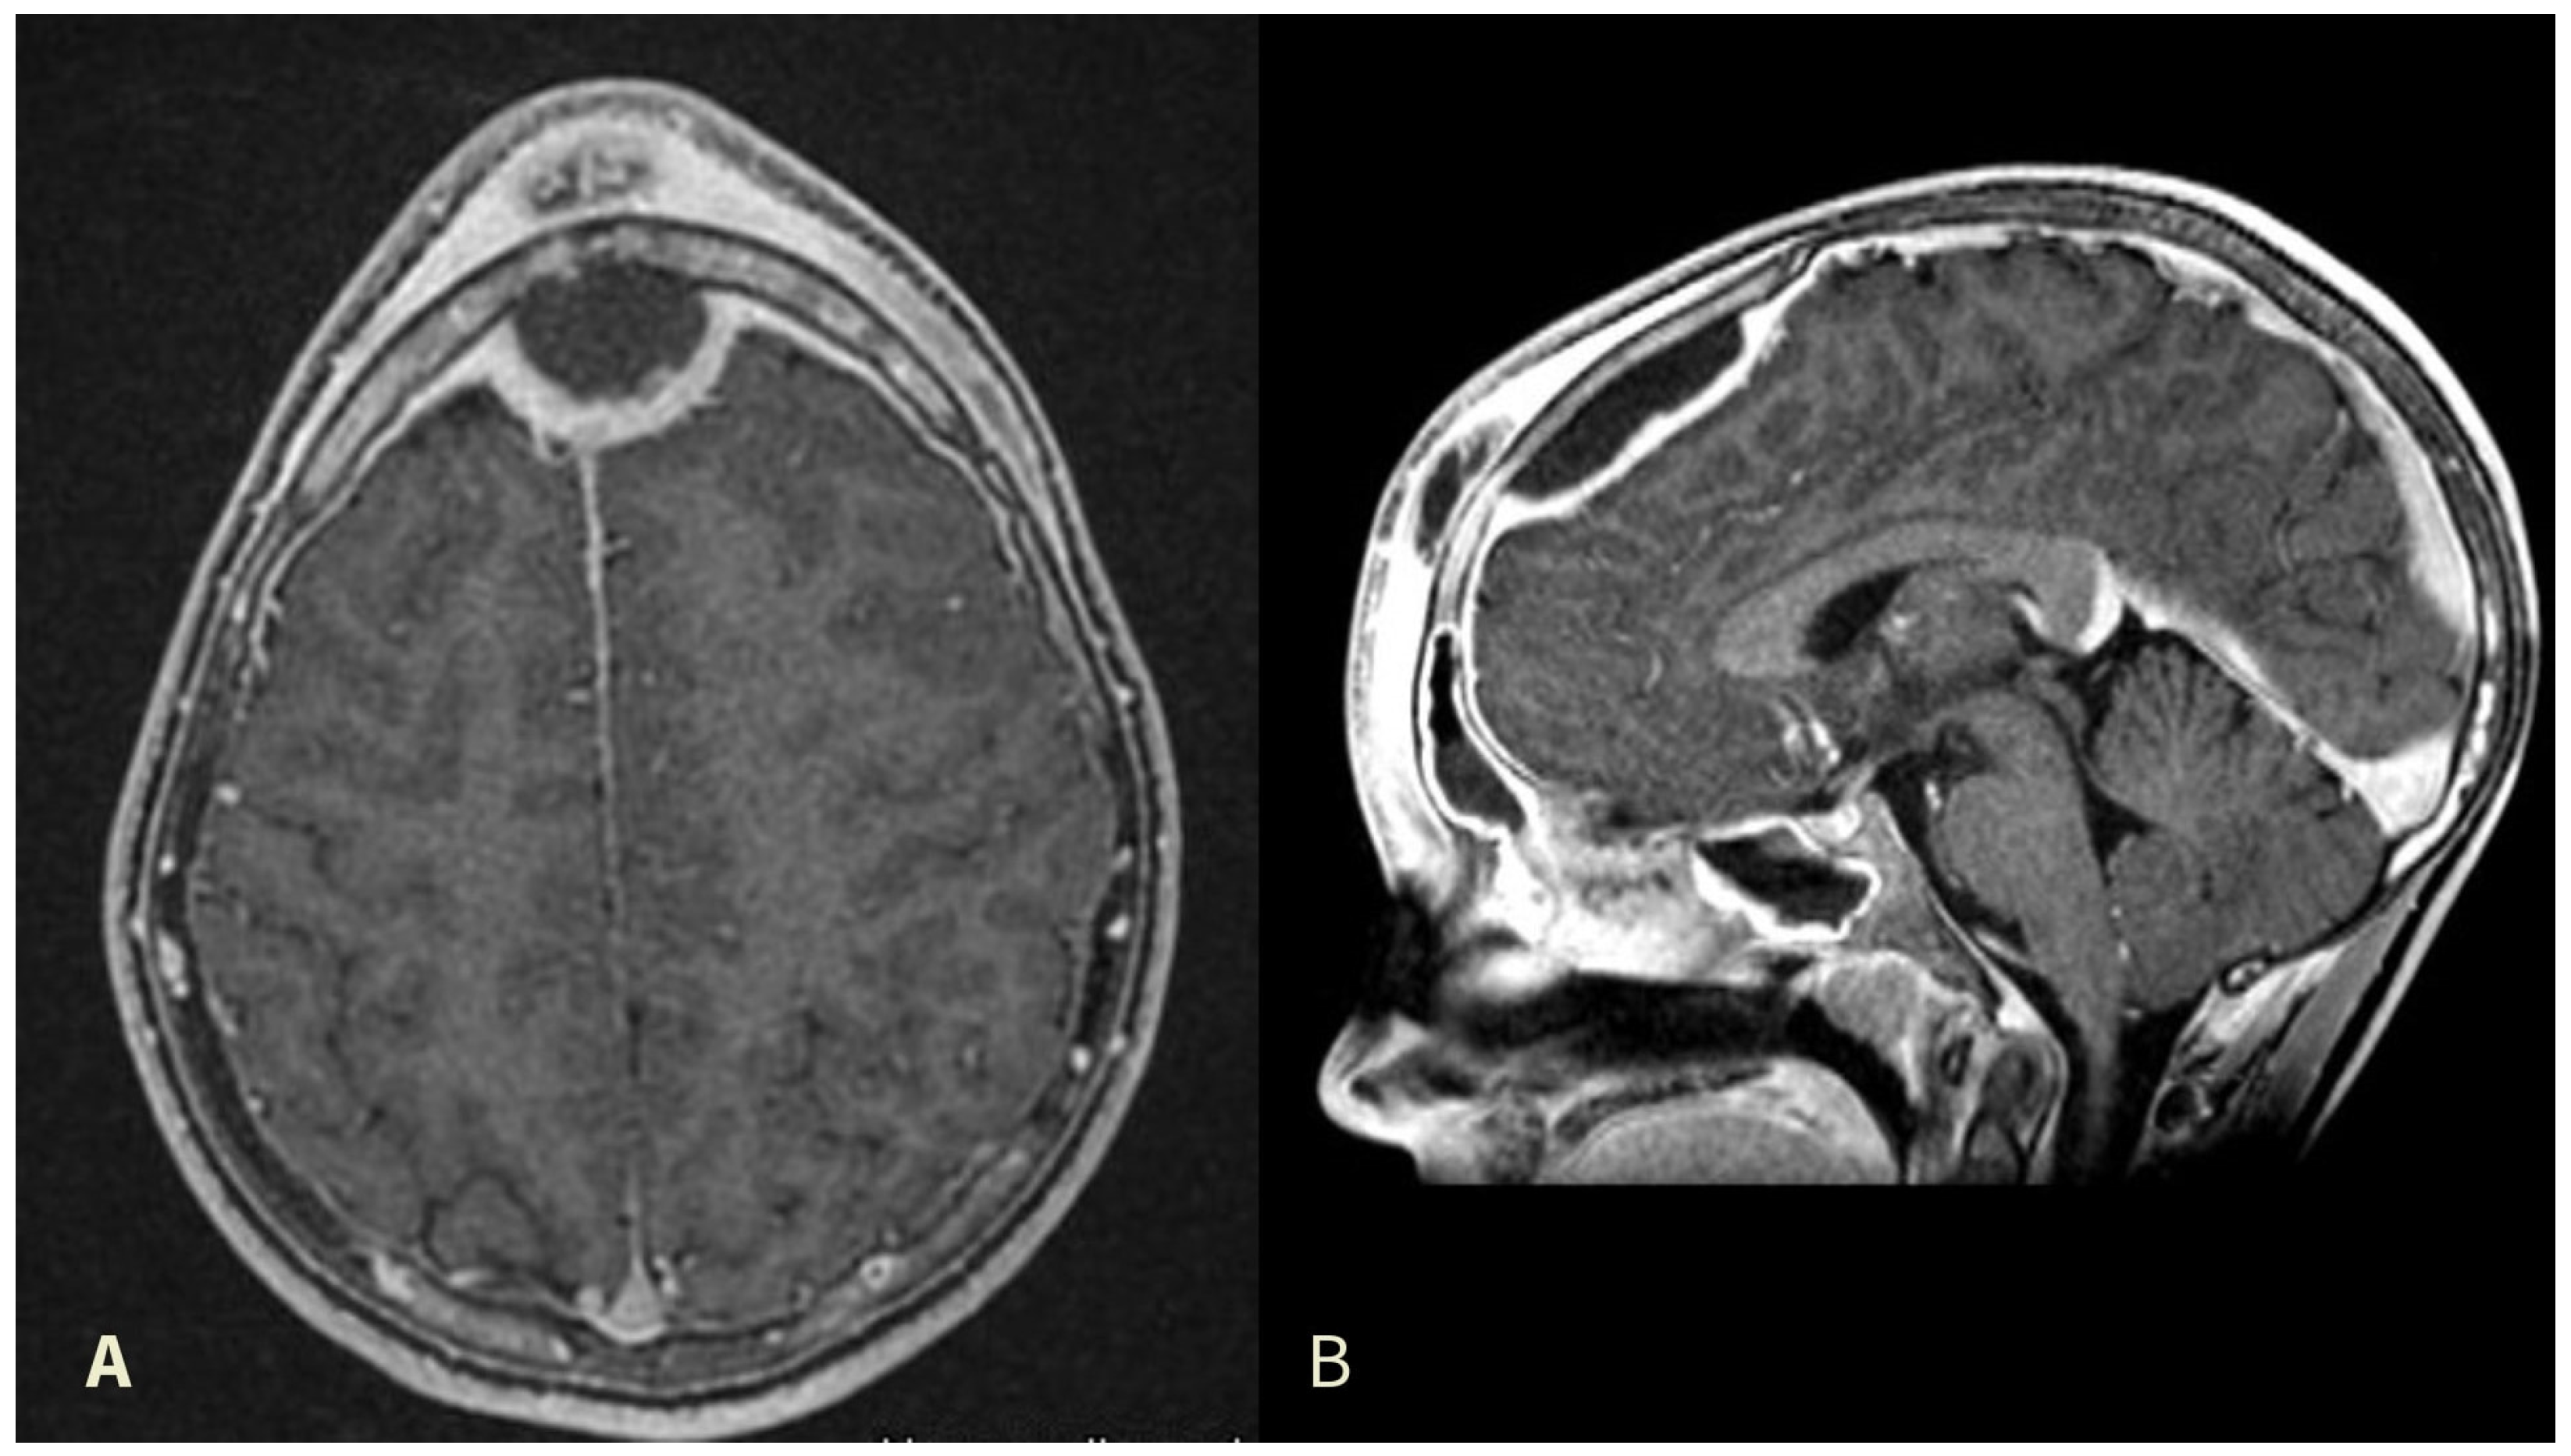

3.1. Case Report

| Our case | 2024 | 12 | M | ARS | ce-CT, ce-MRI | EDA | ESS, CRA | ceftazidime, VAN, MET | S. intermedius |